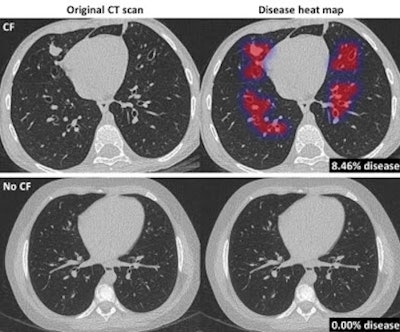

Original CT scan (left) and overlay (heat map; right) of disease areas in the lungs of a CF patient and healthy control, determined in several seconds by Thirona's new Pragma-AI software. Image courtesy of Thirona.With Pragma-AI, Thirona has automated the method so that analysis of CT scans of cystic fibrosis patients can be performed in several seconds without human interference, the company stated.